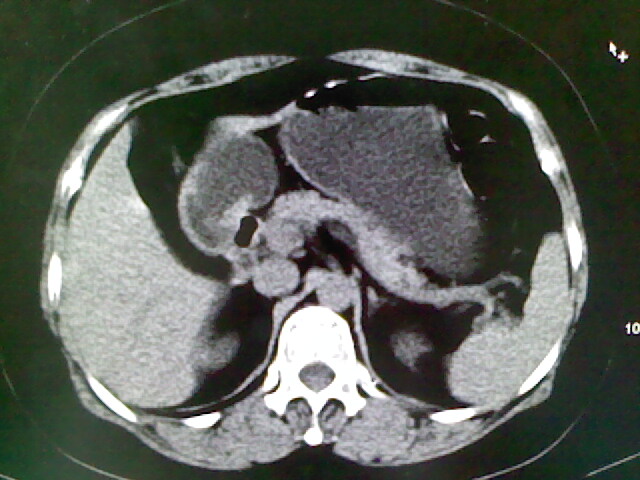

以下是引用卜一在2009-4-2 13:26:00的发言:[br]胆囊颈部结石伴胆囊炎!另:建议增强,待除外肝内占位及胆囊占位!

以下是引用liaoqiang在2009-4-2 16:23:00的发言:[br]胆囊是否切除?胆囊颈区致密影考虑金属夹?结石?肝脏右叶低密度影,考虑增强。